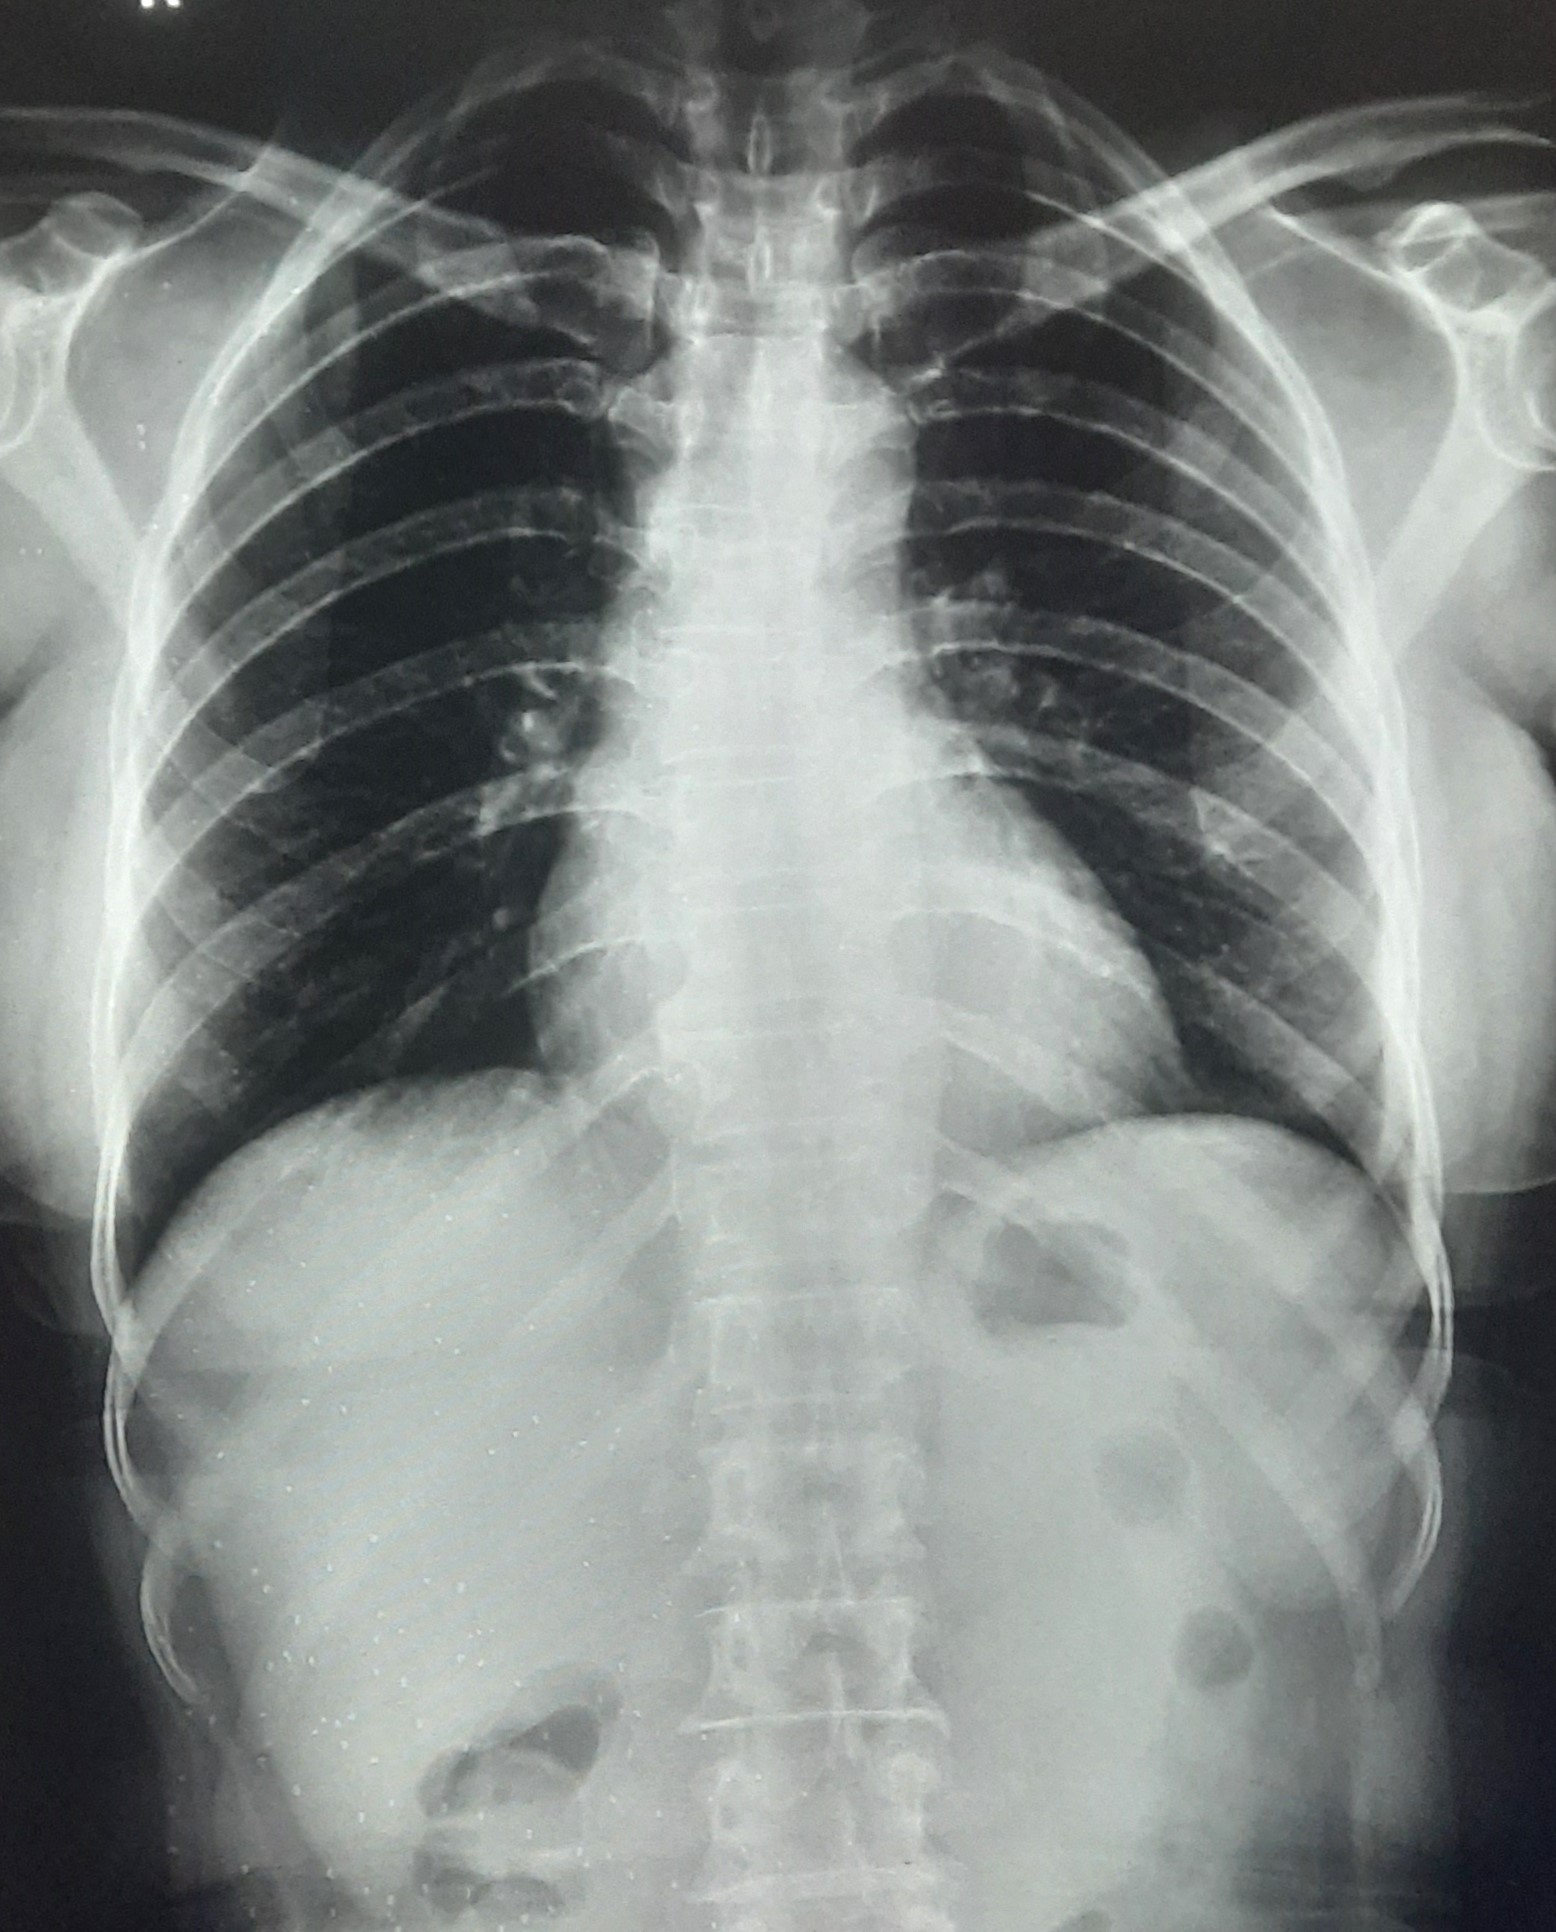

| 251 | IGGMC, Nagpur, Nagpur | P2 | 29-4221 | Ganpat Gaikawad | Consent taken on Paper | 70 Yrs. |

Provisional Diag : post TB sequele?

Final Diag : Fibrosis |

Non-TB Case (Confirmed) | Fibrosis | Abnormality visible on x-ray |